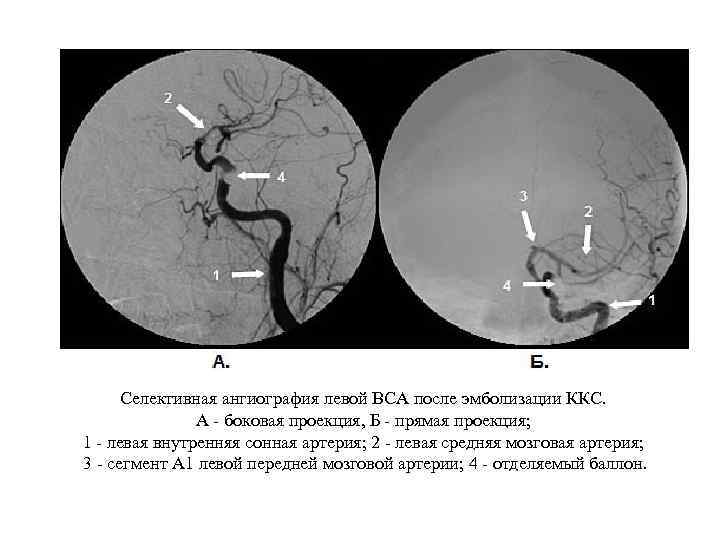

Селективная ангиография левой ВСА после эмболизации ККС. А - боковая проекция, Б - прямая проекция; 1 - левая внутренняя сонная артерия; 2 - левая средняя мозговая артерия; 3 - сегмент А 1 левой передней мозговой артерии; 4 - отделяемый баллон.